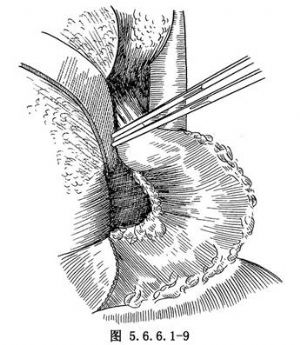

(3)游离胃:探查腹腔,如腹内无明显转移,在胃体上2/3与1/3交界处的小弯侧将胃肝韧带切开,再由相对应的胃大弯侧切开胃结肠韧带,用一条纱带越过胃后将胃向上牵引(图5.6.6.1-4)。继续切开胃结肠韧带,保留胃网膜右动脉,将韧带中的血管钳夹后切断结扎(图5.6.6.1-5)。切开胃脾韧带,切断结扎胃短动脉分支。在暴露术野时注意牵拉脾脏不能用力过大,以免撕裂脾脏(图5.6.6.1-6)。胃大弯侧游离足够以后,离断胃肝韧带,保留胃右动脉(图5.6.6.1-7)。在贲门下方附近的小弯侧摸到搏动的胃左动脉,用3把止血钳夹住,近侧两把,远侧1把,切断后先缝扎一道,再由其深部结扎一道(图5.6.6.1-8),缝扎胃侧血管断端。如此时胃左动脉近侧残端有出血,应先用指压住出血点,再请第一助手以拇指用力按压胸主动脉即可止血,用吸引器将积血迅速清除后,即可从容寻找到出血处予以处理。小弯侧游离完后,在离断贲门之前,请麻醉师将胃管连接在吸引器上持续吸引,将胃内容物尽量吸净,如此可以减少污染并方便吻合操作,吸引完后将胃管向外拔,使其尖端置于贲门上方3~4cm处。用大号直止血钳夹住贲门切断(图5.6.6.1-9)。胃侧断端用中号丝线贯穿缝合,再将浆肌层对拢间断缝合。食管侧断端用贯穿缝合封闭后用阴茎套保护之。将游离完毕的胃提至胸腔。